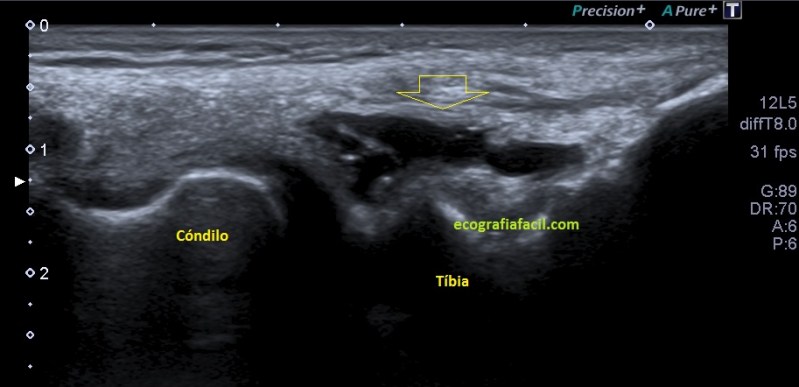

Que debemos encontrar, bien, algo parecido a esto:

Esta es la normalidad, es una imagen preciosa cedida por Javier Álvarez @fisioequilibra, TSID, Fisioterapeuta, Profesor de la Universidad Francisco de Vitoria de Madrid, colaborador del Blog y amigo de los que se cuentan con los dedos de la mano…

Es lo primero que debes buscar, es lo más importante. En la imagen  1 puedes ver un menisco normal y sano, señalado por la flecha hueca amarilla. Semiológicamente es una estructura cónica hiperecogénica, homogénea en la cara externa de la rodilla entre la tibia y el cóndilo femoral, profundo al ligamento colateral, es la parte visible del menisco por ecografía y es tu objetivo en cada exploración de esta zona.